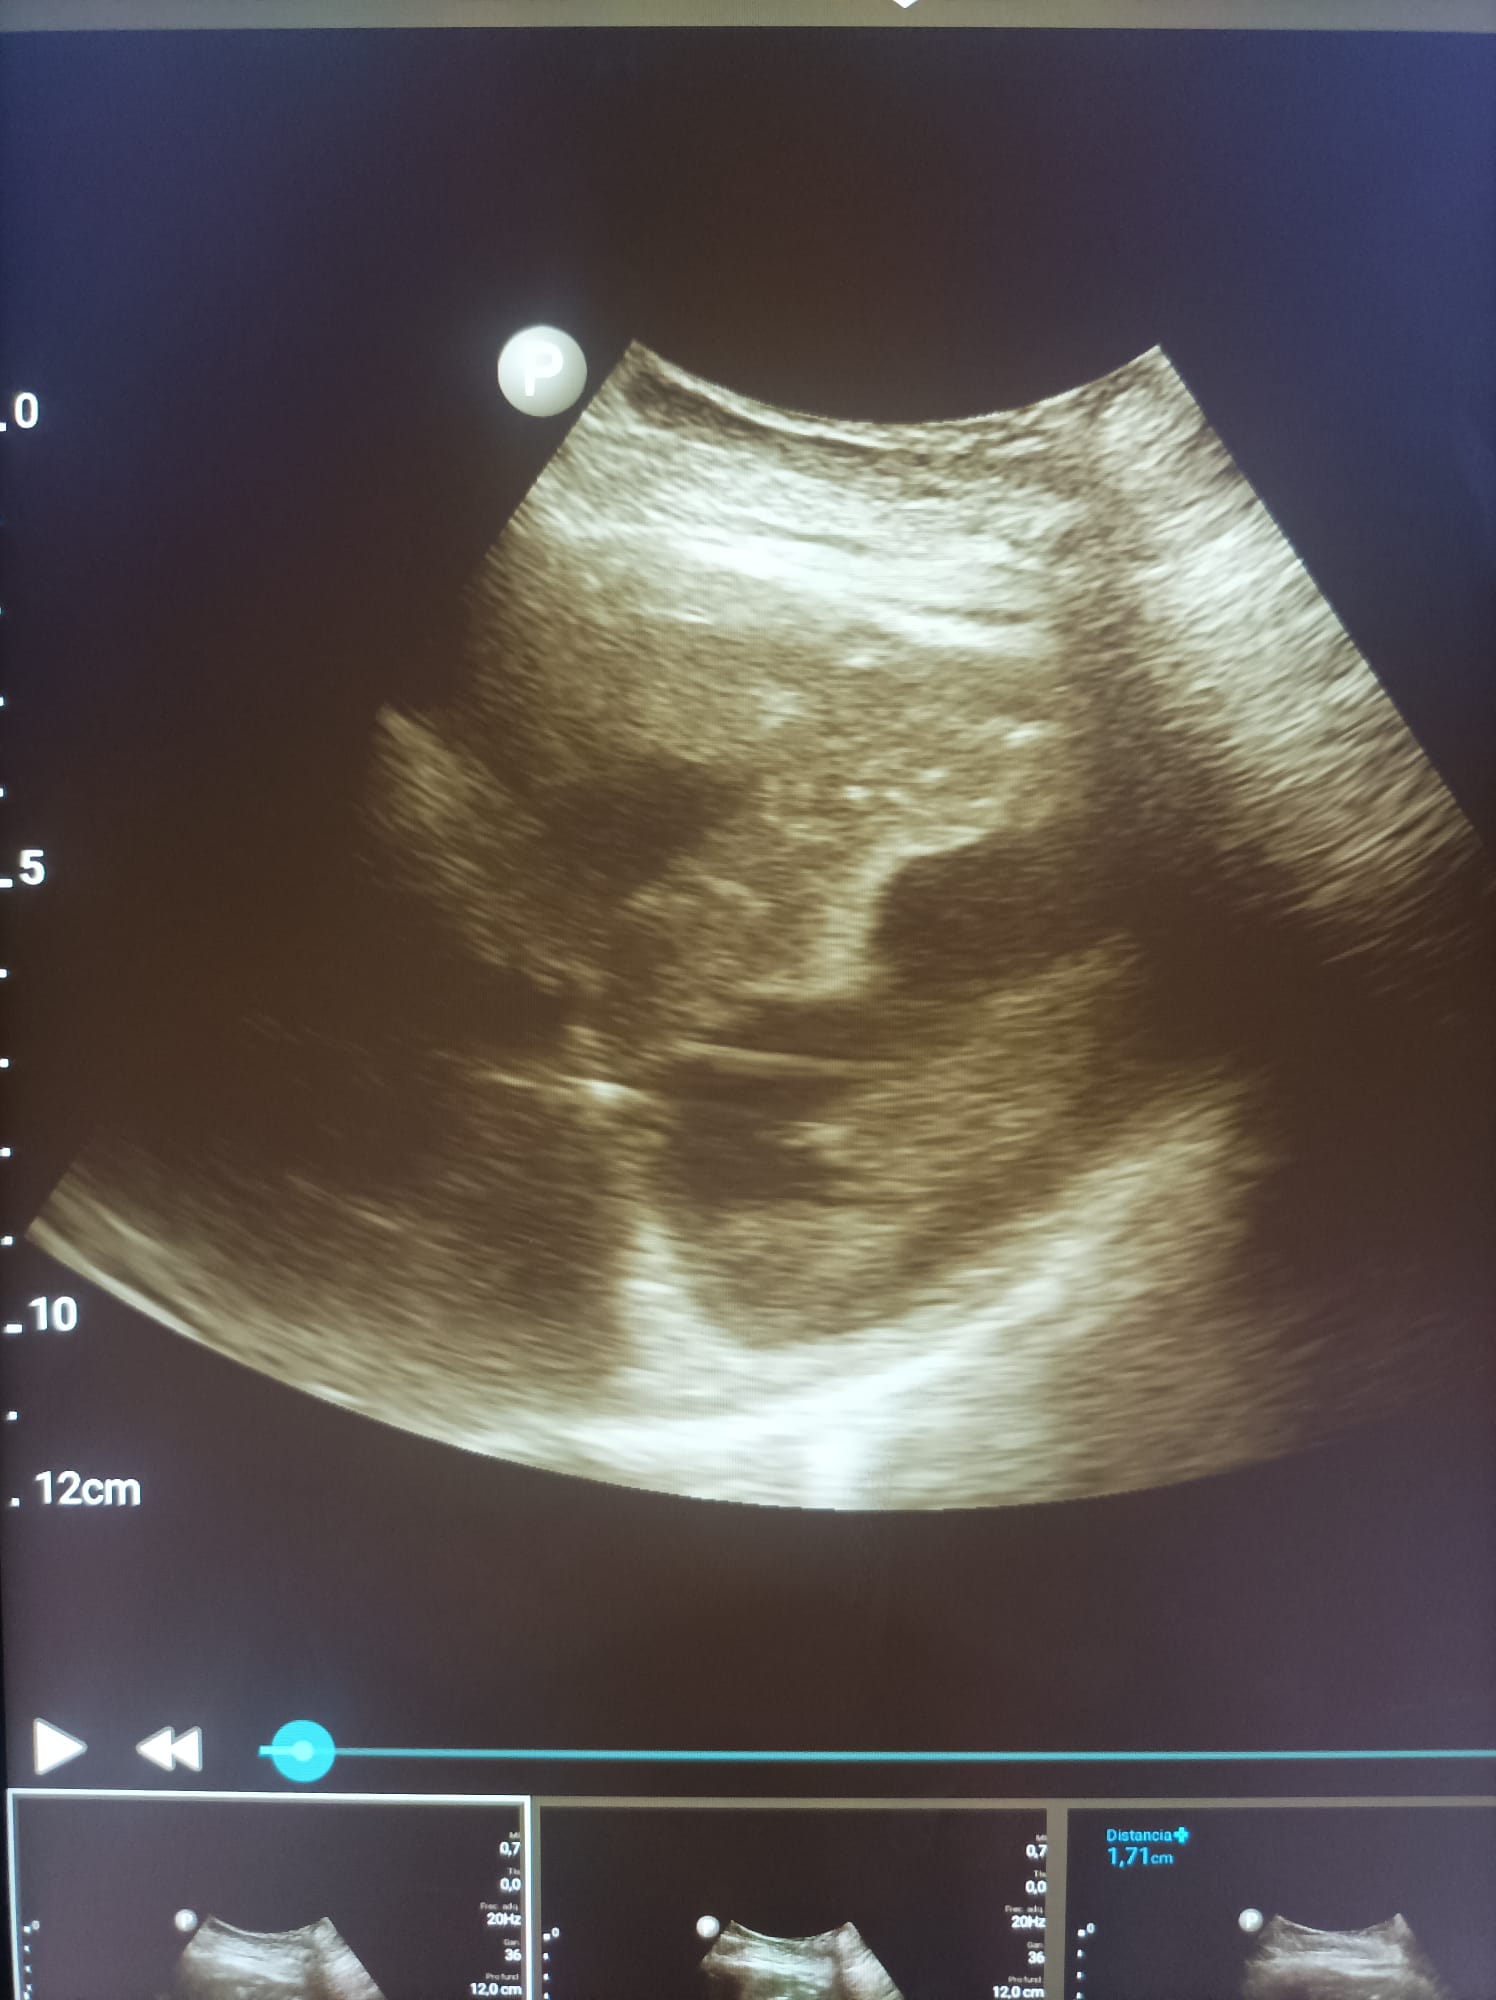

Disponíamos de una sonda convexa que nos ha permitido la realización de ecografías abdominales, pulmonares e incluso obstétricas en diferentes ámbitos; servicio de urgencias, servicio de cirugía general y medicina interna.

Las patologías mas prevalentes han sido la ascitis y la insuficiencia cardiaca, asi como pacientes politraumatizados que se han beneficiado de FAST a su entrada en urgencias.

Otras patologías diagnosticadas han sido: abscesos hepáticos, derrames pleurales, tumores hepáticos, abortos espontáneos e incluso miocardiopatía hipertrófica.

Además de diagnósticos, hemos podido realizar ciertas técnicas invasivas como paracentesis e incluso toracocentesis eco guiadas, disminuyendo asi las complicaciones secundarias a las mismas.